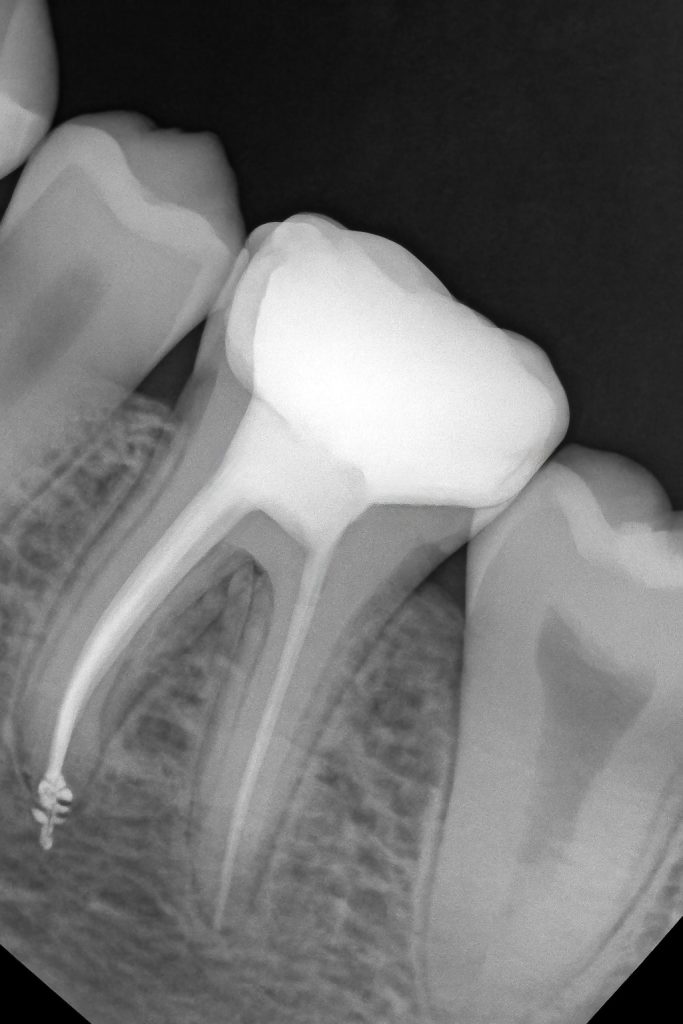

4. Endodontic Workflow

(Images 7–10)

- Canal scouting and glide path creation.

- Working length confirmed radiographically.

- Rotary instrumentation with copious NaOCl and EDTA.

- 3-cone fit verification.

- Warm vertical obturation with bioceramic sealer for deep tubular penetration and a tight apical seal.

- Post-endo radiograph confirms excellent fill and apical control.